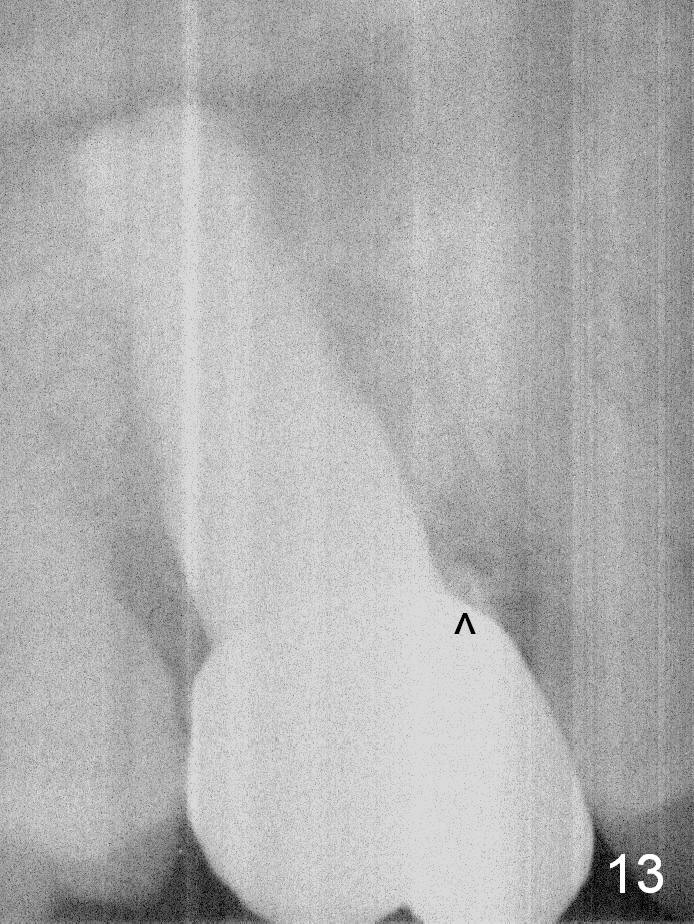

The implant remains stable 2.5 months postop without abnormal bone resorption (Fig.9). Since the provisional has dislodged on several occasions, impression is taken for final restoration. When the provisional is removed 3 months postop, the margin of the restoration is shown to be subgingival (Fig.10 arrowheads), but is distinctly separated from the gingiva. This is due to the presence of the provisional (its margin were fabricated slightly deeper). The provisional is also intentionally fabricated slightly larger than the final restoration. When the latter is cemented, there is space to remove extra cement trapped subgingivally (Fig.11). No cement is visible post cementation (Fig.12 (C: crown)). Eighteen months post cementation, the patient returns for recementation. After laser gingivectomy and Panavia resin bonding, PA shows residual cement (Fig.13 ^). After repeated removal with Piezo scaler and explorer, the residual cement appears to be smaller, which is ignored at the time of X-ray taking (Fig.14 ^). More dismayed is tight mesial contact. Water pik is recommended. When peri-implantitis develops later on, make an incision for cement removal. If the crown is dislodged soon, check whether the existing abutment is loose, remove acrylic in the access hole and remove the abutment. Install a new 4x3 mm one. Trim the abutment carefully and more on the opposing tooth.